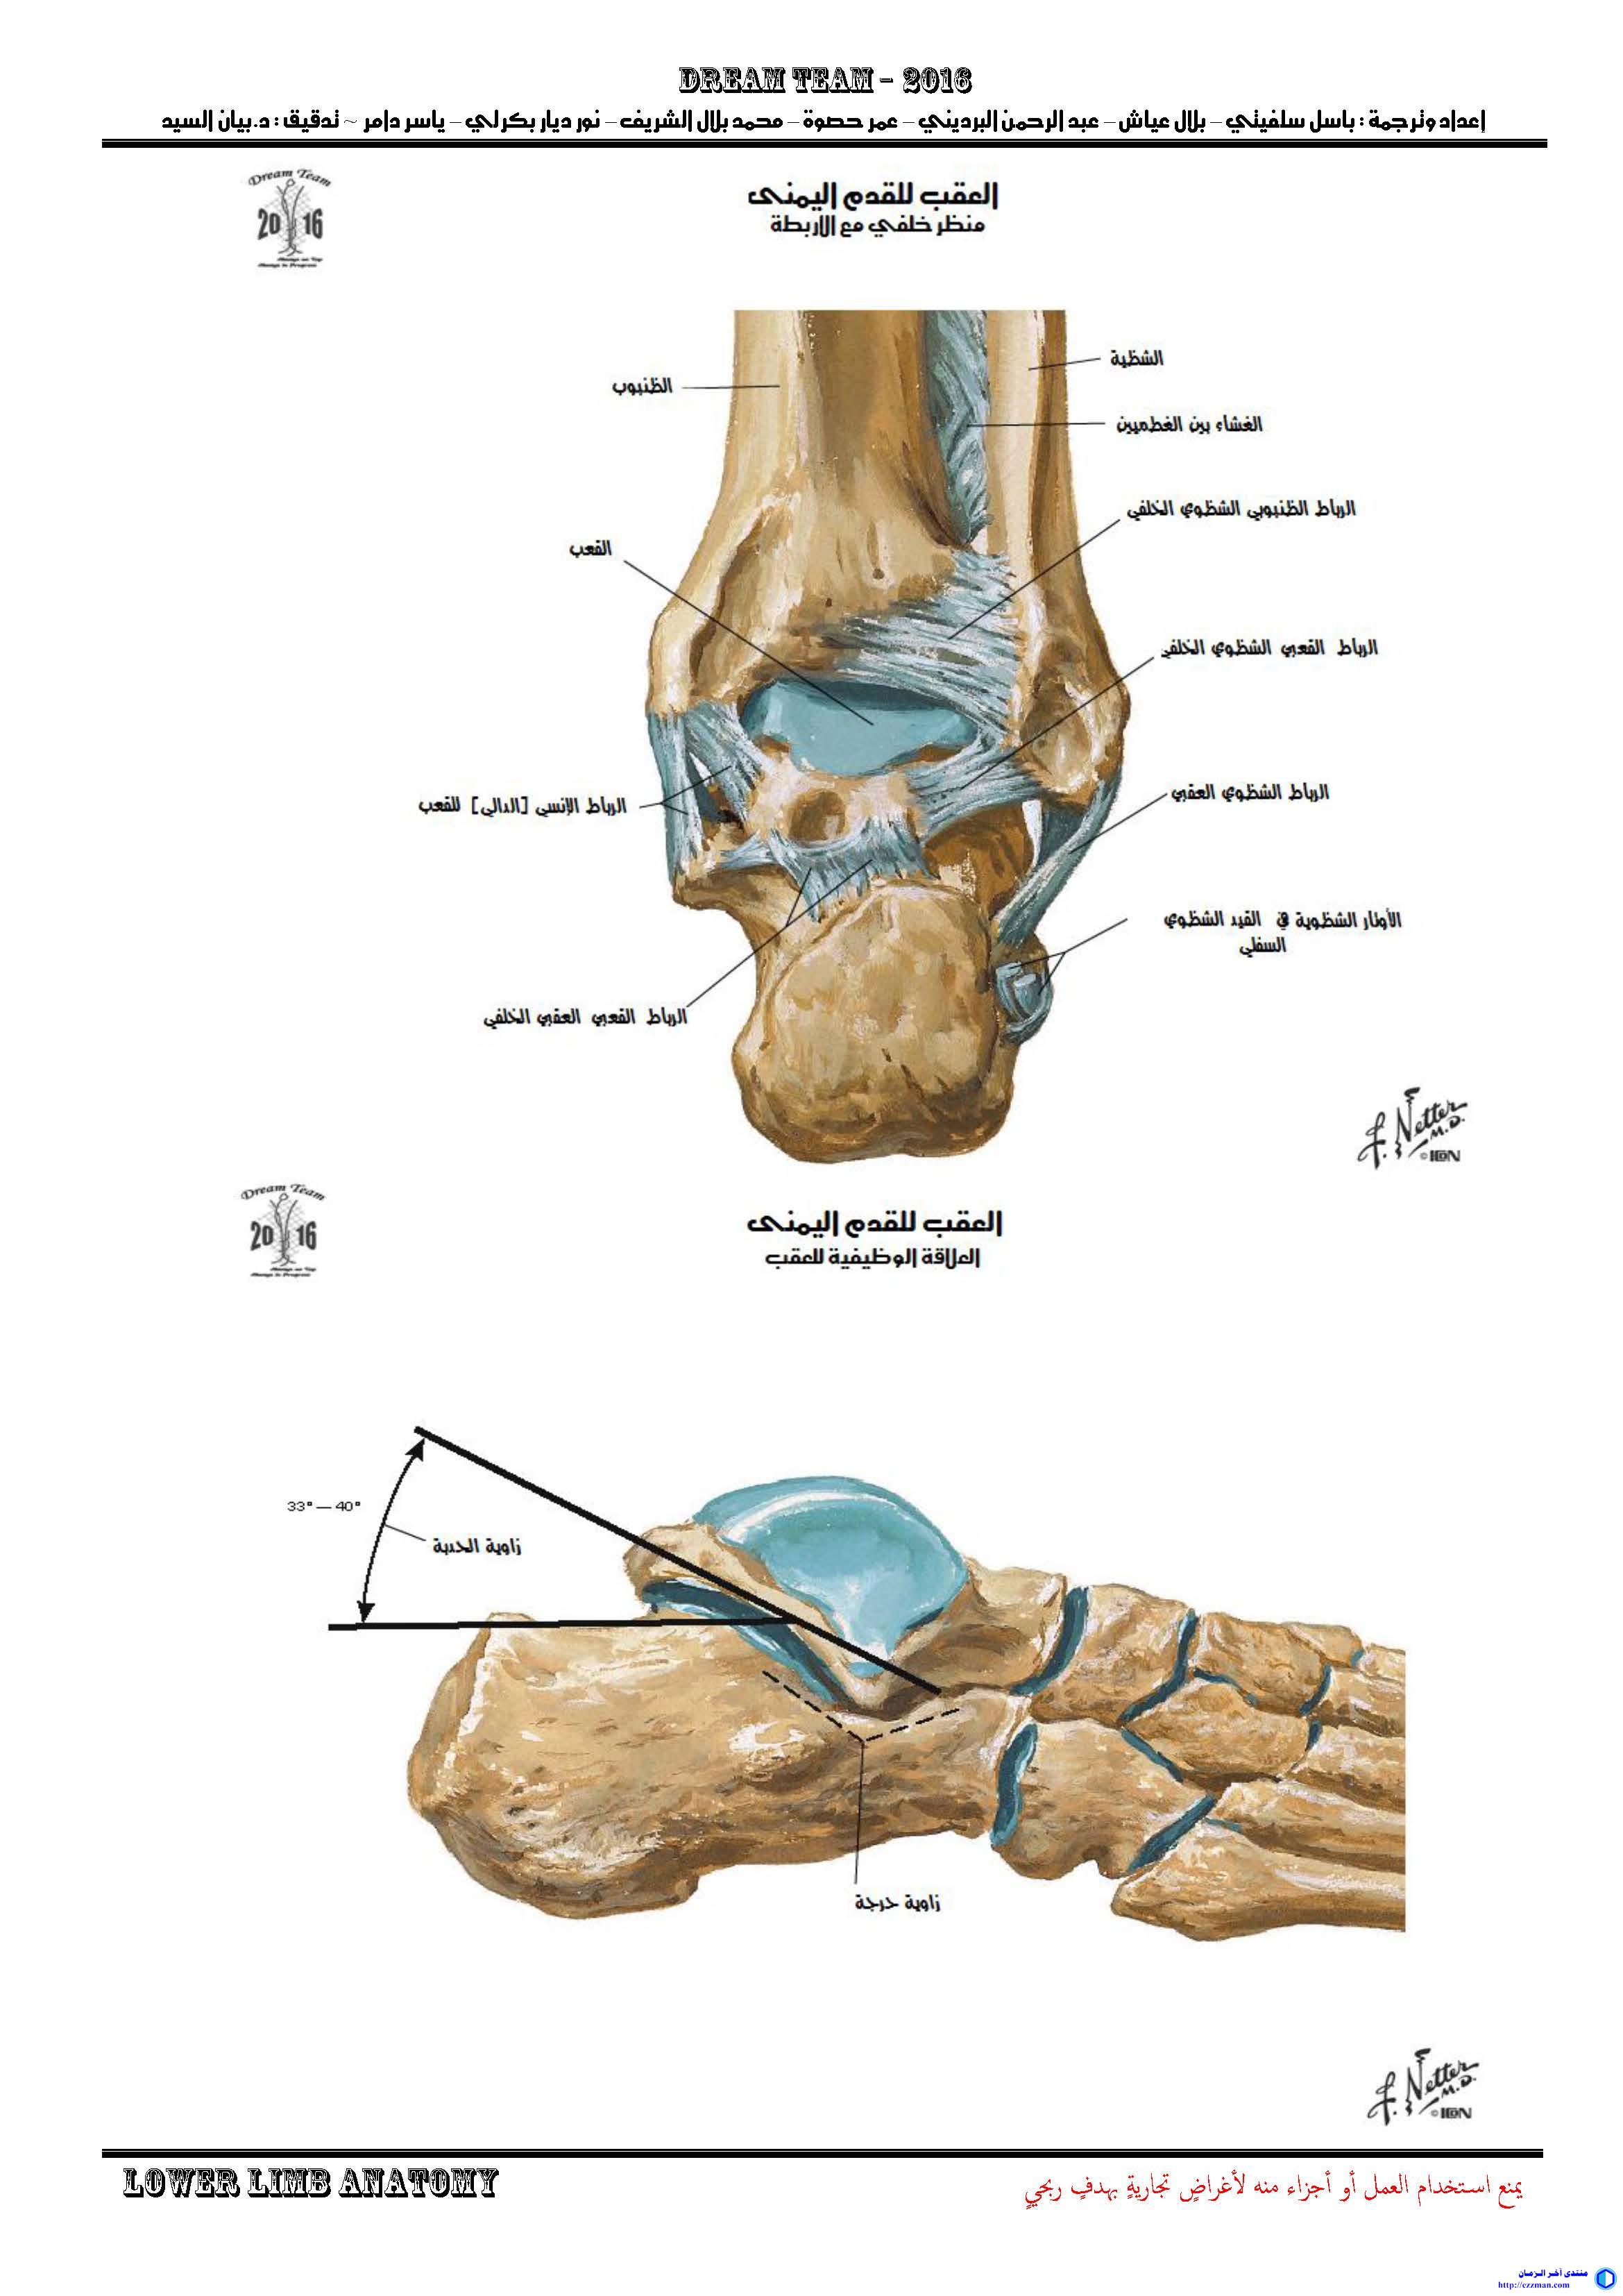

-   -   أطلس التشريح Netter [الجزء 8 الطرف السفلي] (https://www.ezzman.com/vb/t3726/)